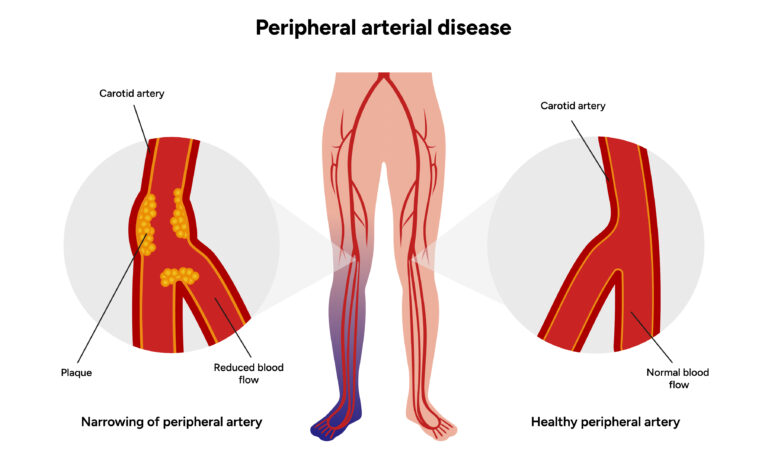

Peripheral Artery Disease (PAD) is a serious condition where the arteries supplying blood to the legs and feet become narrowed or blocked due to plaque buildup (atherosclerosis). This results in reduced blood flow, causing leg pain, difficulty in walking, non-healing ulcers, and in severe cases, risk of amputation.

- Atherosclerosis (cholesterol/plaque deposits in arteries)

Signs and Symptoms of PAD

- Leg pain or cramping while walking (claudication)

- Numbness or weakness in legs

- Coldness in lower leg or foot compared to the other side

- Slow-healing wounds, sores, or ulcers

- Change in skin color (pale, bluish, shiny)

- Weak or absent pulse in feet